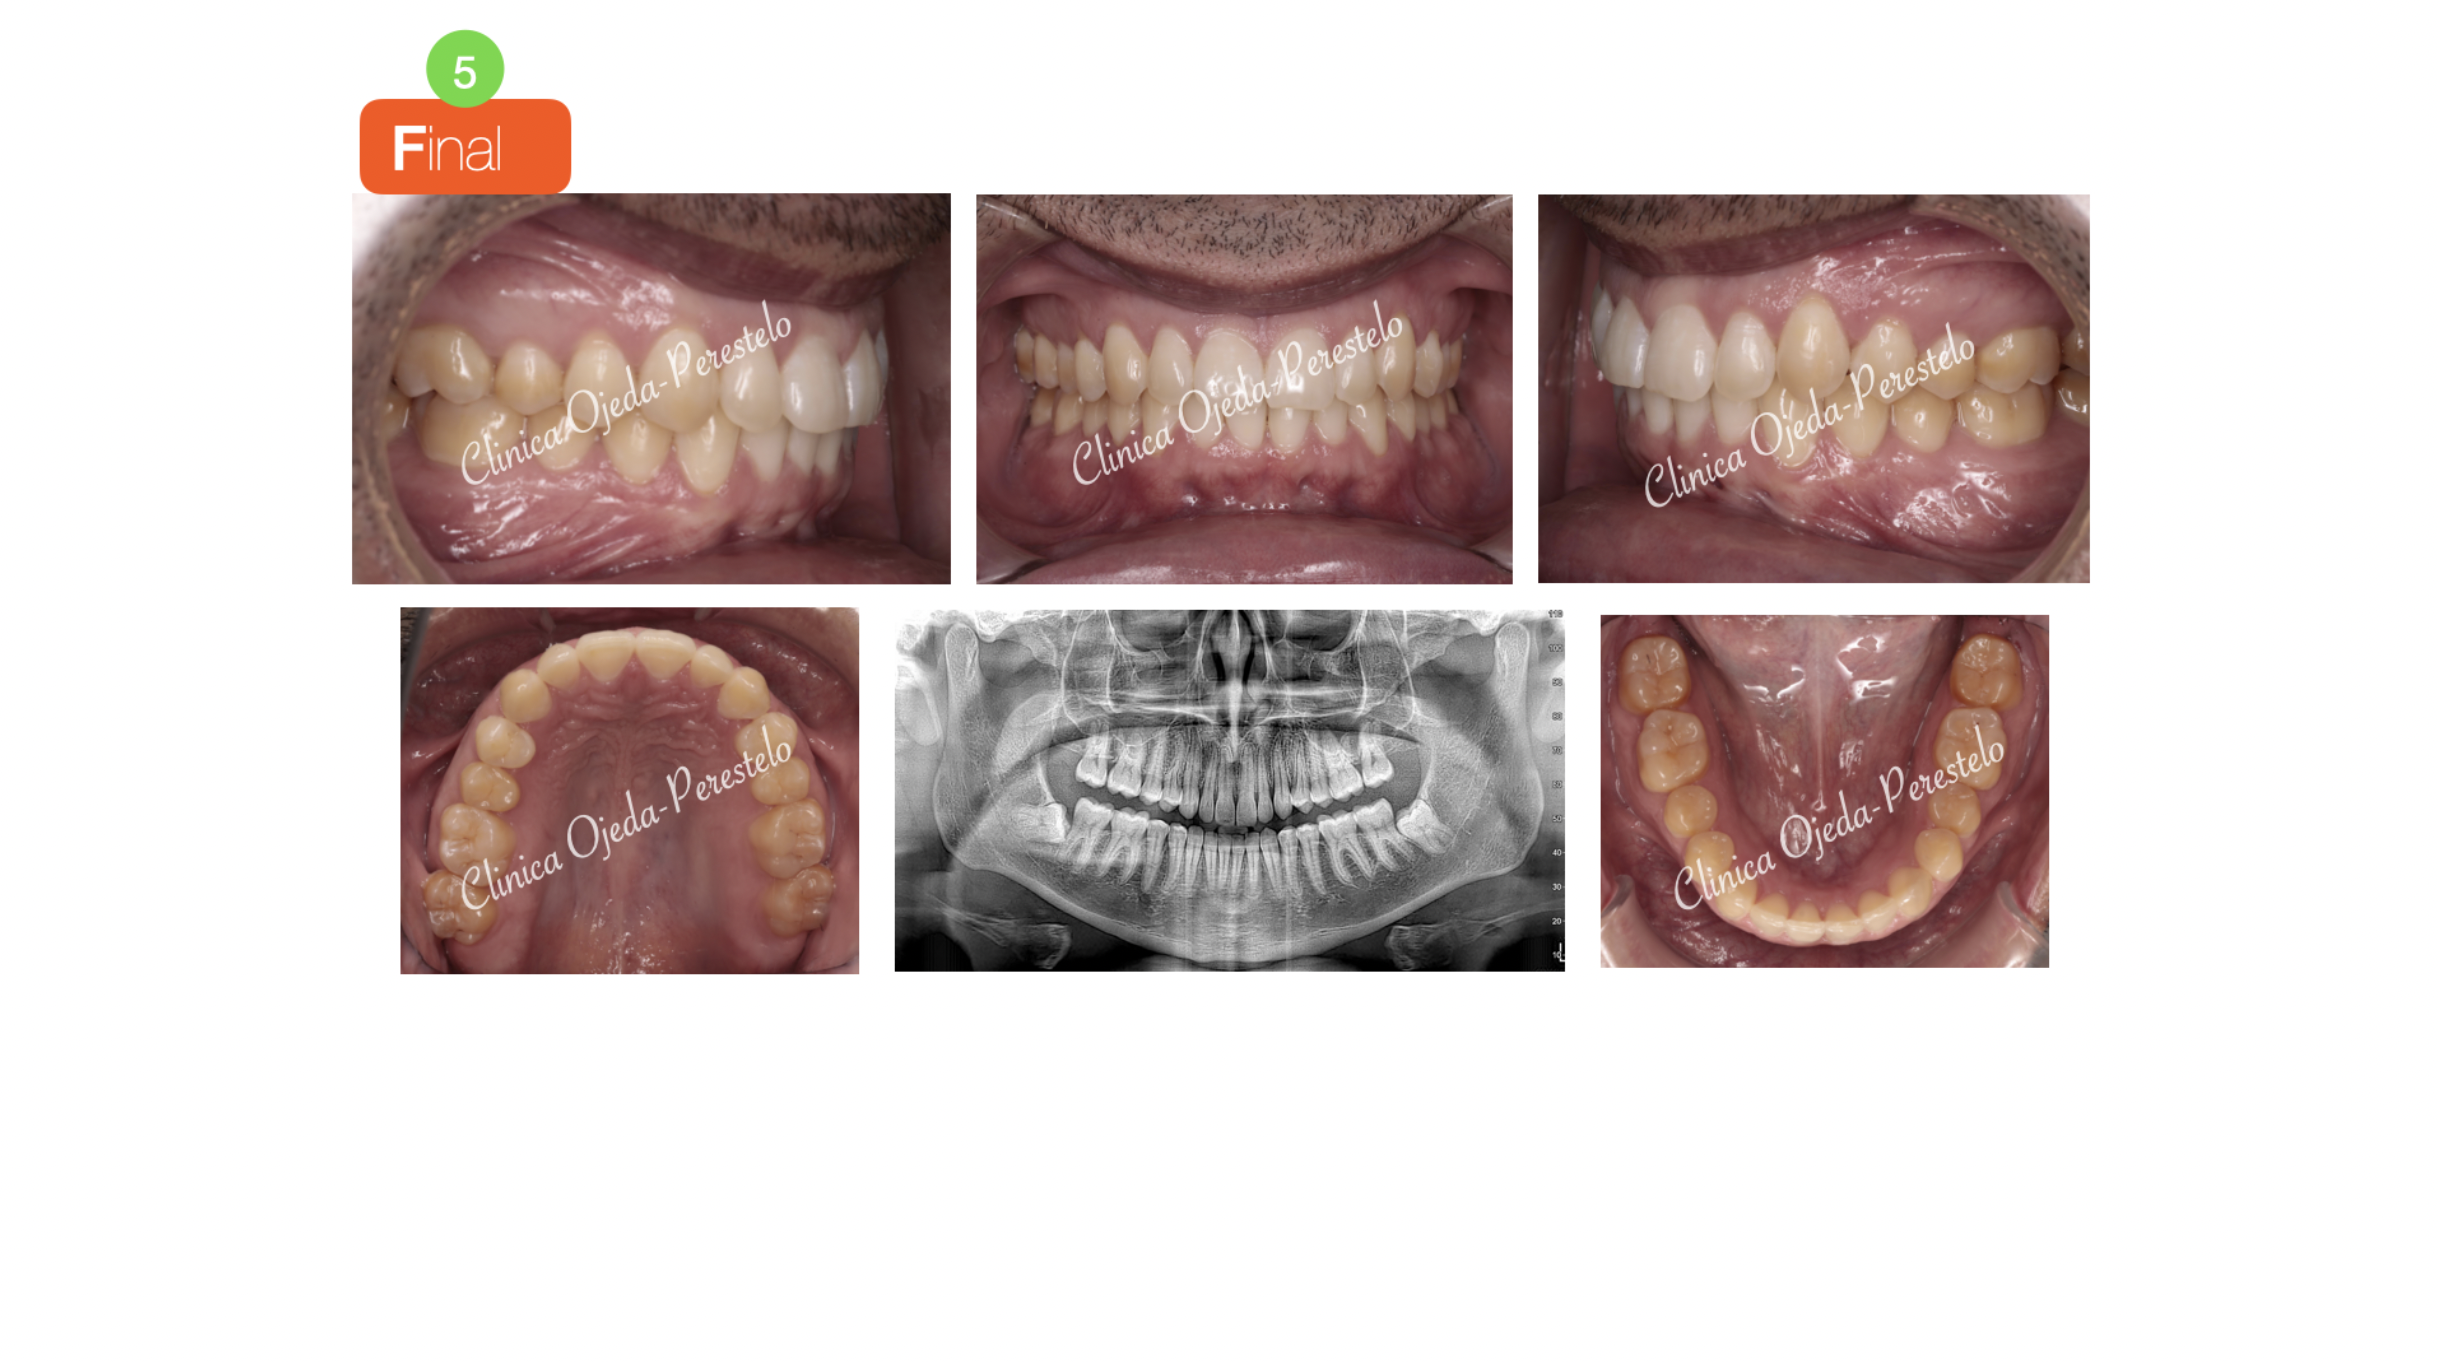

Finalmente destacar la mejora de la sonrisa con un correcto centrado de las lineas medias. Su articulación dentaria es correcta presentando una cinemática mandibular adecuada.

El objetivo se ha alcanzado con 107 alineadores superiores y 82 alineadores inferiores realizandose los cambios semanalmente